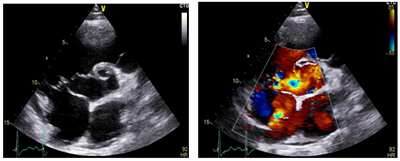

33 years old male patient, smoker, with a history of treated asthma , left posttraumatic pneumothorax with repeted pleurodesis, solved by surgery is admitted for dyspnea at rest, dry cough accentuated in clinostatism and cyanosis, symptoms that worsened two months before admission, onset two years ago. The clinical examination revealed a left latero-thoracic postsurgical scar, mixt cyanosis, rest dyspnea, dry cought, normal pulmonary auscultation, SpO2=97%, anterior chest pain, turgid jugular veins, tachycardia, BP=130/70mmHg, left parasternal continuous murmur of high intensity, accentuated by Valsalva maneuver, loud S 2 palpable in pulmonary area, systolic tricuspid murmur, no edemas, hepatomegaly and hepato-jugular reflux. Electrocardiogram (Figure 1) showed sinusal tachycardia, 120bpm, right bundle branch block, right axis deviation. The blood samples revealed myocardial and hepatic cytolyse, increased creatinine. On chest X-ray as showed in Figure 2 we found cardiomegalia, straight left middle cardiac arch, pulmonary stasis, latero-basal pachypleurites and left fissure inflamation. Performing the transthoracic ecocardiography (Figure 3a-3c) we noted normal LV systolic function, enlargement of the right cavities and pulmonary artery, mild mitral regurgitation, medium-mild pulmonary regurgitation, moderate functional tricuspidian regurgitation, noncoronary Valsalva sinus aneurysm ruptured into the RA with hemodynamic significant left to right shunt and mild pericardites. The contrast echocardiography found slow opacification of the right cavities without comunication between right and left cavities. During Valsalva maneuver on echocardiography air bubbles are visible into the right cavities with dissapearance after 10minutes of left lateral decubitus, during this event the patient`s dyspnea becomes more intense. The thoracic CT scan fails to find a broncho-vascular fistula. The transesophageal echocardiography better defines the communication without other congenital defects. Abdominal ultrasound reveales mild ascites and hepatosplenomegalia. He receives treatment with antialdosteronic and loop diuretic, unfractioned heparine, beta blockers , bronchodilator and intermitent oxygenoterapy. The patient is transferred for the surgical repair with good evolution and hemodynamic compensation. During surgery no other defects or fistulas were identified. On follow-up the patient was stable with mild pulmonary hypertension, one episode of atrial flutter and no signs of heart failure.1‒3

Figure 3a LV hypertrophy with normal function, asymmetry of the aortic cusps, dilated coronary sinus, mild pericardial effusion, normal mitral valve.

Figure 3b Pulmonary artery dilatation with mild regurgitation and pulmonary hypertension, PAPm=32mmHg.

Figure 3c Tricuspid aorta, non-coronary sinus aneurysm communicating with the RA, left to right shunt; mild aortic regurgitation.